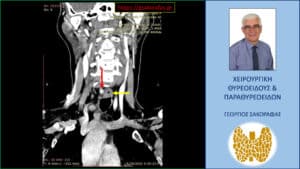

Λόγω επιμένοντος PHPT και με δεδομένους τους περιορισμούς των δύο βασικών διαγνωστικών εξετάσεων (υπερηχογράφημα και σπινθηρογράφημα) παραπέμφθηκε για περαιτέρω έλεγχο με τετραδιάσταση αξονική τομογραφία (4D-CT) όπου περιγράφεται μόρφωμα με διαστάσεις 9 x 7.5 x 5 mm παρά τον οισοφάγο, σε επαφή με την προσπονδυλική περιτονία, στο ύψος του Α6 σπονδύλου, πίσω από την τραχεία και την δεξιά κοινή καρωτίδα.

H εικόνα είναι συμβατή με έκτοπο αδένωμα παραθυρεοειδούς.

Απεικόνιση του αδενώματος (κόκκινο βέλος) σε κατά μέτωπο διατομή στην 4D-CT σε διαφορετικό επίπεδο. Απεικονίζεται σε παρακείμενη θέση και ο οισοφάγος (κίτρινο βέλος)